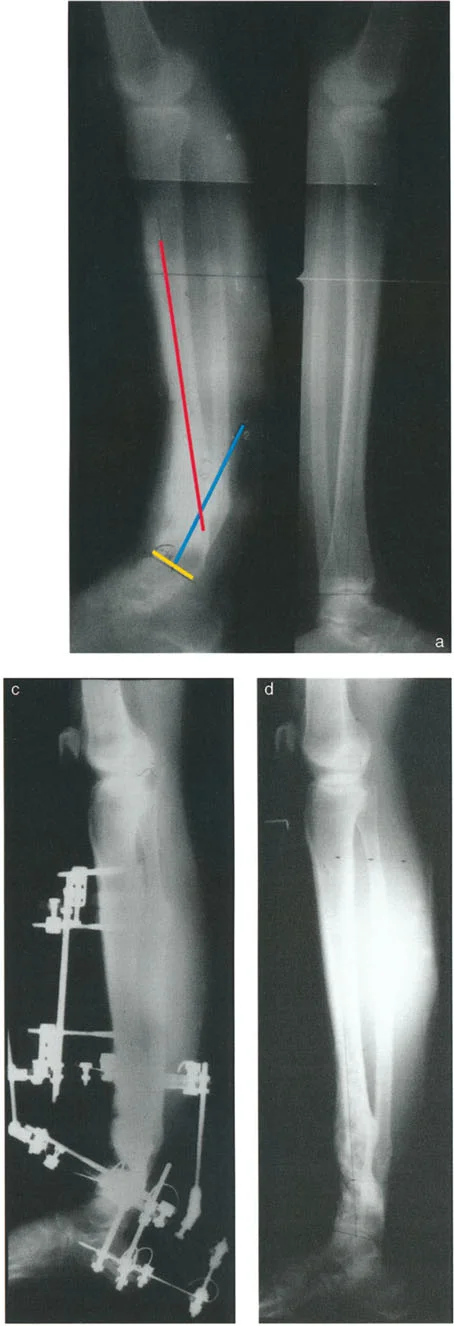

* الأشعة السينية (X-rays) الواقفة لكامل الطرف السفلي: هذه الأشعة ضرورية لتقييم المحاذاة الكلية للطرف السفلي تحت تأثير وزن الجسم. يطلب الأستاذ الدكتور محمد هطيف صورًا شعاعية كاملة الطول للساق أثناء الوقوف (Full-length standing alignment films) لتقييم المحور الميكانيكي للساق وتحديد زوايا المفاصل بدقة.

* الأشعة السينية الجانبية والامامية الخلفية للكاحل: تُظهر هذه الصور تفاصيل مفصل الكاحل نفسه، بما في ذلك زاوية القصبة الأمامية البعيدة (ADTA) وزاوية القصبة الوحشية البعيدة (LDTA)، وهي زوايا حاسمة لتحديد التشوه في المستويين الأمامي والسهمي.

* رسم المحاور الميكانيكية والتشريحية: لتحديد نقطة مركز دوران التشوه (CORA)، وهي النقطة التي يجب أن تتم عندها الجراحة لتصحيح التشوه بأقل قدر من المضاعفات.

تُعد مبادئ الدكتور درور بالي حجر الزاوية في جراحة تصحيح تشوهات العظام. تركز هذه المبادئ على تحديد "مركز دوران التشوه" (CORA - Center of Rotation of Angulation) بدقة. إن موقع CORA يحدد كيفية تأثير التشوه على المفاصل المجاورة ويوجّه الجراح في اختيار مكان قطع العظم (Osteotomy).

1. القاعدة الأولى: عندما يمر قطع العظم ومحور تصحيح الزاوية (ACA) عبر CORA، يتم تحقيق تصحيح زاوي نقي دون أي إزاحة.

2. القاعدة الثانية: عندما يمر ACA عبر CORA، ولكن قطع العظم يتم في مستوى مختلف (غالبًا ما يكون ضروريًا لتوفير مساحة كافية للتثبيت)، يتم تحقيق تصحيح زاوي نقي، ولكن أطراف العظم ستنزاح في موقع قطع العظم. يجب على الجراح توقع هذه الإزاحة وإدارتها.

3. القاعدة الثالثة: إذا كان ACA وقطع العظم في نفس المستوى، ولكن لا يمر أي منهما عبر CORA، فسيحدث تشوه إزاحة (ترجمة) غير مرغوب فيه. يتطلب هذا الأمر من الجراح إجراء إزاحة متعمدة للقطعة العظمية البعيدة أثناء التصحيح الزاوي لإعادة محاذاة المحور الميكانيكي.